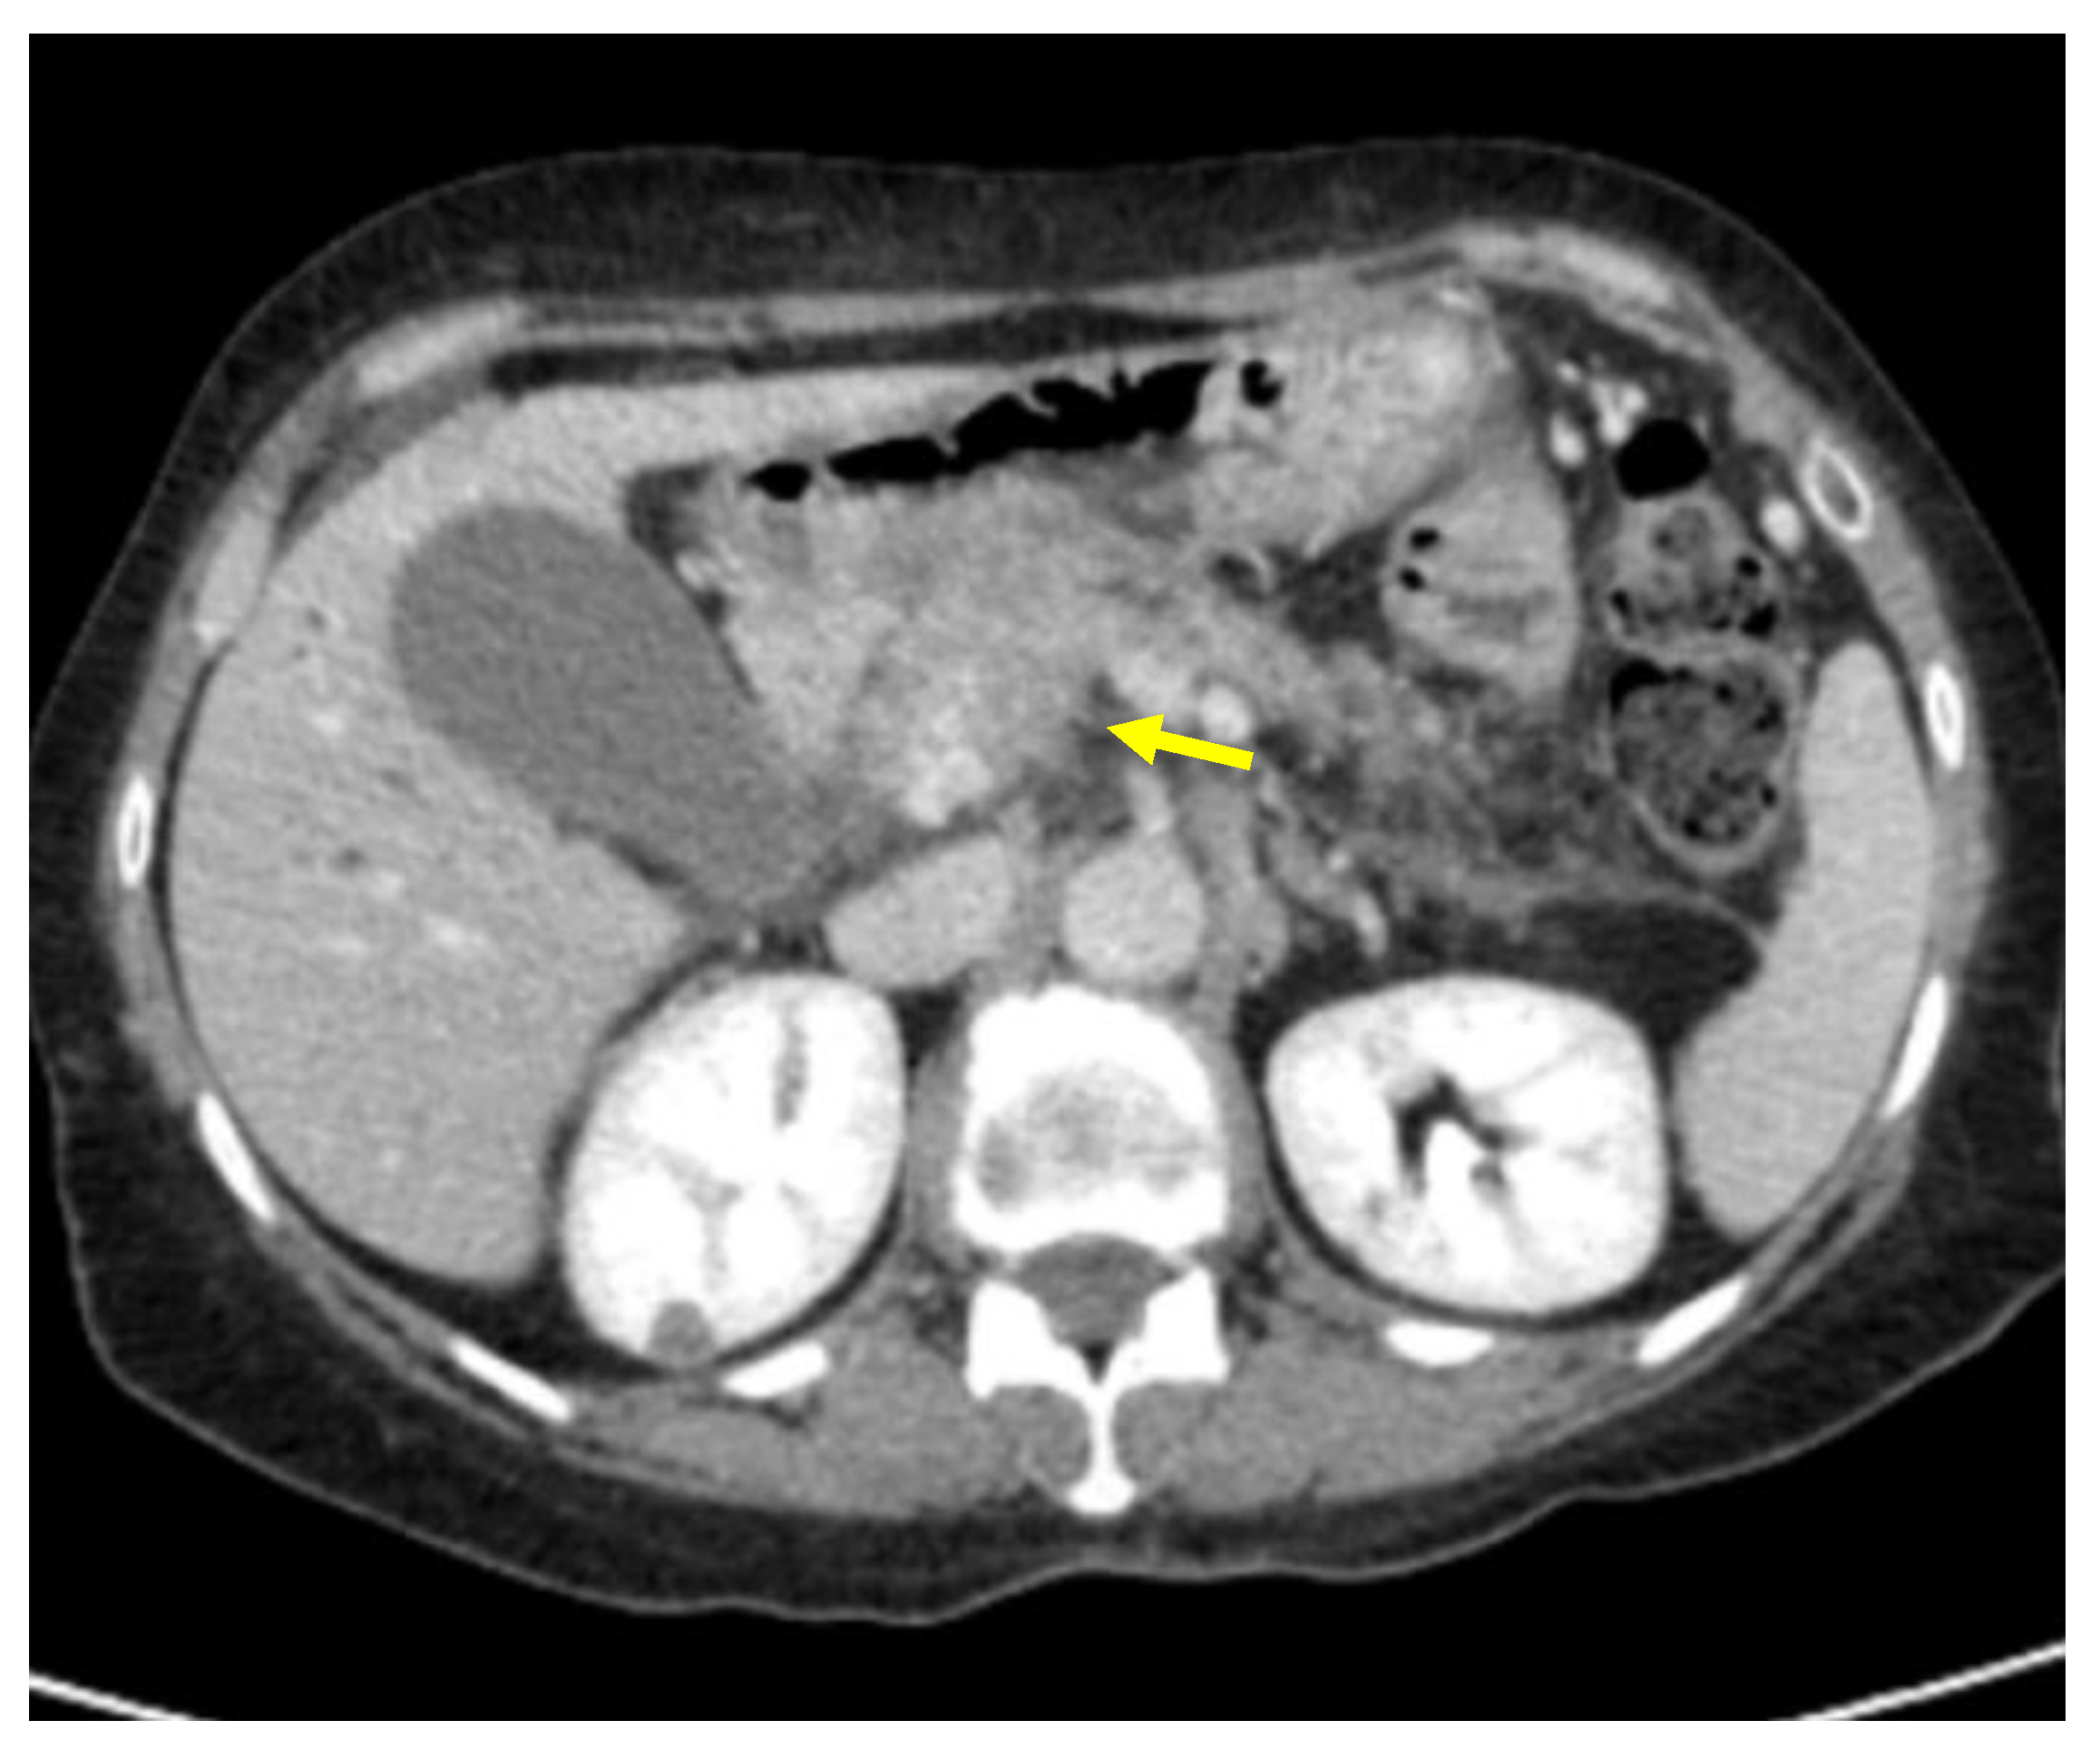

Tumor margins showed a significant difference in the two groups, appearing well-defined in only 6 (6.98%) metastatic patients and ill-defined in the remaining 80 (93.02%); in the non-metastatic group, the margins appeared well-defined in 132 (65.35%) and ill-defined in 70 (34.65%) tumors (Figure 2, Figure 3, Figure 4 and Figure 5).

Figure 4. Pancreatic lesion with ill-defined margins (arrow) on CT examination in pancreatic contrast phase.